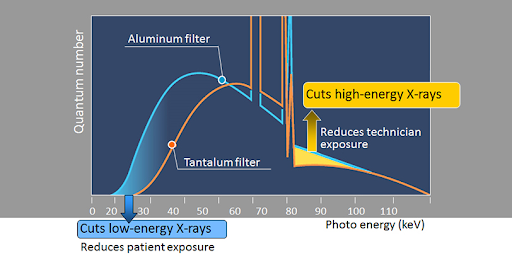

Танталовый фильтр

Фильтр уменьшает излучение низкой и высокой энергии для уменьшения дозы облучения пациента и дозы рассеянного излучения, получаемой оператором.